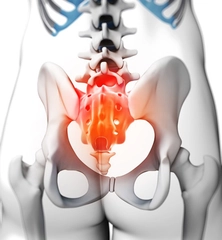

Cervikal OmurgaCervikal omurga, boyun bölgesinde bulunan yedi omurdan oluşmaktadır (C1-C7). Bu bölge, başın hareketini ve başın ağırlığını dengelemeye yardımcı olur. Özellikle C1 ve C2 omurları, başın dönmesini sağlayan özel yapılar içerir. Cervikal omurgada meydana gelen herhangi bir yaralanma ya da dejenerasyon, baş dönmesi ve sinir kökü sıkışması gibi klinik durumlardan kaynaklanan semptomlara yol açabilir. Thorakal OmurgaThorakal omurga, on iki omurdan (T1-T12) oluşur ve göğüs kafesini destekler. Bu bölgedeki omurlar, kaburgalarla bağlantılıdır ve bu nedenle göğüs boşluğunun stabilitesine katkı sağlar. Thorakal omurgada meydana gelen deformiteler, genellikle kifoz veya skolioz gibi duruş bozukluklarına yol açabilir. Lumbar OmurgaLumbar omurga, bel bölgesinde bulunan beş omurdan (L1-L5) oluşur. Bu bölge, vücut ağırlığını destekler ve hareketliliği artırır. Lomber omurga, en sık yaralanma ve dejenerasyon geçiren bölgedir. Lomber disk herniasyonu, bel ağrısı ve siyatik gibi problemlerle ilişkilidir. Sakral OmurgaSakral omurga, beş birleşik omurdan (S1-S5) oluşur ve pelvis ile bağlantılıdır. Bu bölge, vücudun alt kısmına destek sağlar ve hareketliliği azaltır. Sakral omurga, doğum sırasında önemli bir rol oynar ve sakral ağrı gibi klinik durumlarla ilişkilendirilebilir. Omurga Çeşitlerinin Ayırt EdilmesiOmurga çeşitlerinin ayırt edilmesi, aşağıdaki yöntemler kullanılarak gerçekleştirilir: